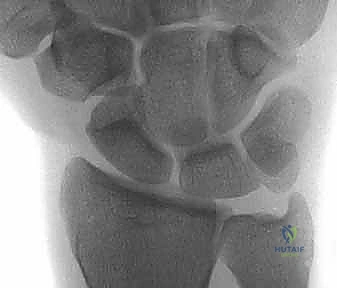

يُسبب تشوه DISI، الذي يتميز بتمدد العظم الهلالي غير المرتبط وانثناء الزورقي، اتساعًا واضحاً في المسافة الزورقية الهلالية (تُعرف إشعاعياً بعلامة تيري توماس "Terry Thomas sign") وتغييراً جذرياً في حركية الرسغ. إذا تُركت هذه الحالة دون علاج احترافي من قبل طبيب متمرس كالدكتور محمد هطيف، فإنها تؤدي حتماً إلى هجرة العظم الرأسي (Capitate) للأسفل بين العظمتين المنفصلتين، مما يطلق سلسلة من التآكل الغضروفي السريع الذي ينتهي بـ الانهيار المتقدم للرسغ الزورقي الهلالي (SLAC wrist)، وهي حالة تتطلب جراحات إنقاذية كبرى مثل دمج مفصل الرسغ.

- التصوير بالأشعة السينية (X-rays): يتم أخذ صور شعاعية في وضعيات متعددة (أمامية خلفية، جانبية، وبقبضة مغلقة Clenched Fist View). وضعية القبضة المغلقة تزيد الضغط على المفصل وتُظهر بوضوح الفجوة بين العظمين (علامة تيري توماس) إذا كان الرباط ممزقاً.